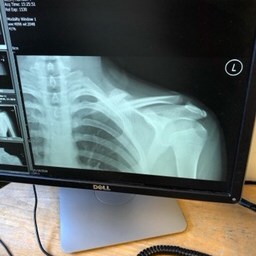

On a personal note this year has been brought much drama, We have had 3 broken bones, a collarbone in August and both Fibula and Tibia broken in November resulting in surgery with a nail inserted through H’s right leg. The road to full recovery will be long, both physically and mentally but ‘H’ is one tough cookie and I have witnessed an inner steel in him that will stand him in great stead for the future, literally !